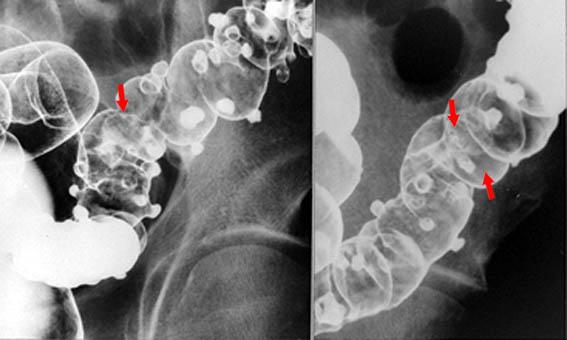

Criteria of Hist.ClassificationDiverticulum/Multiple Diverticulum

LocationLarge intestine(Colon)/Descending colon

Technique, MethodX-ray

Size10 - 14